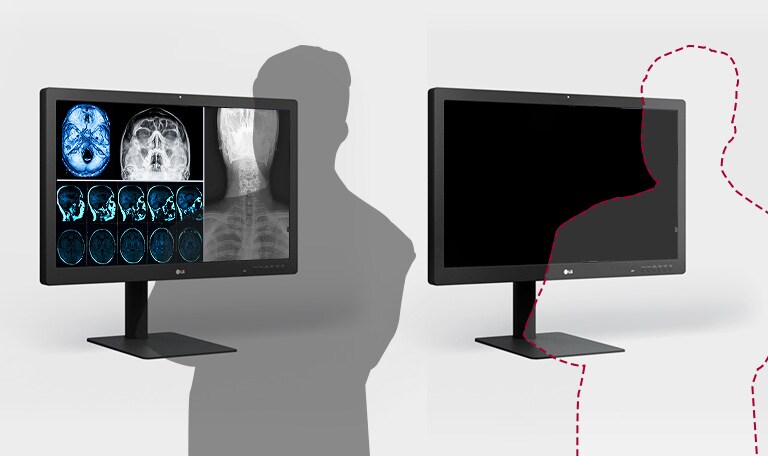

LG 31.5-inch 8MP IPS Black

Diagnostic Monitor

Presence Sensor

YES